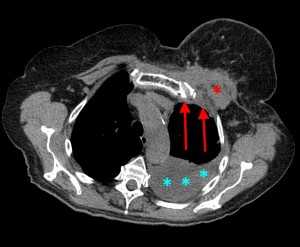

Лимфогенные метастазы на рентгене и КТ выглядят как множественные мелкие очаги с диссеминированным распространением, локализованные в междольковых перегородках, в плевральных листках. Вокруг можно видеть характерную картину ракового лимфангиита. Кроме того, практически всегда выявляются патологически измененные и увеличенные лимфатические узлы средостения. Лимфогенное метастазирование необходимо дифференцировать с милиарным туберкулезом, саркоидозом. Иногда это требует привлечения Второго мнения.

КТ: метастазы в легких при раке молочной железы. На изображении справа красной звездочкой отмечен опухолевый узел в молочной железе, красными стрелками - область прорастания опухоли в грудную стенку. Синими звездочками отмечен карциноматозный плеврит — скопление жидкости в плевральной полости. Слева стрелкой отмечен вторичный узел.

Лимфогенные метастазы проявляются увеличением лимфатических узлов средостения в сочетании с мелкоочаговой диссеминацией с очагами до 2-3 мм в диаметре вблизи плевры и в междольковых перегородках, а также по ходу бронхов и сосудистых пучков.